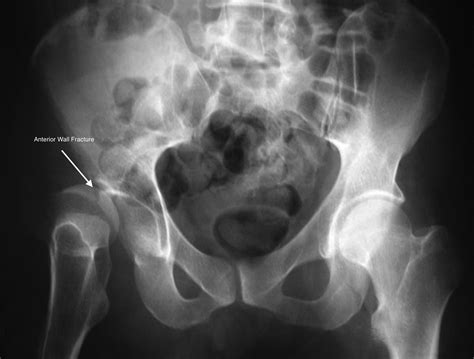

Anterior Wall Fracture of the anterior wall of the acetabulum

Diagnosis of Fractures of the Acetabulum

Diagnosing fractures of the acetabulum involves a combination of clinical examination and imaging studies. The diagnostic process typically includes:

• X-rays: Initial imaging to visualize the fracture pattern and assess the extent of the injury.